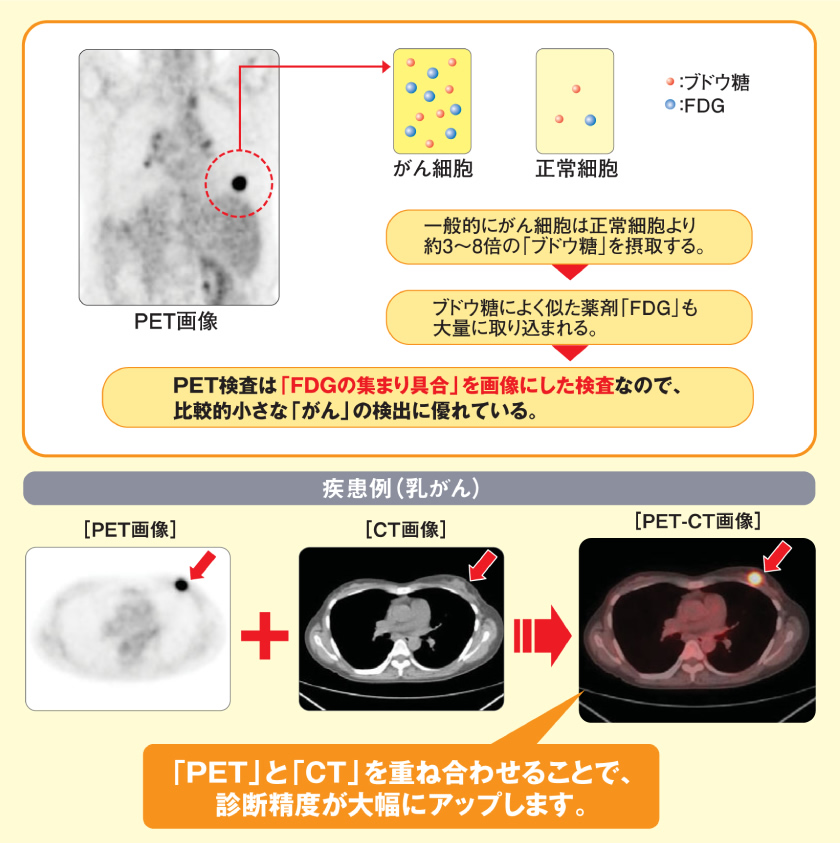

PET-CT検査の有効性

- 「FDG」を用いたPET-CT検査では、ブドウ糖が細胞に取り込まれる過程である「糖代謝」を画像にしているため、「糖代謝」のあまり盛んでないがんなど、種類によってはあまり得意としないがんもあります。また、腎臓や膀胱といった正常でも薬剤が集まってしまう部位(生理的集積部位)の診断には向いていません。そのため、他の検査と組み合わせることによって、存在部位や範囲、重症度がより明確に分かるようになることがあります。以上の点から、PET-CT検査だけでなく他の最適な検査法を併用して最良の診断を受けることをおすすめします。